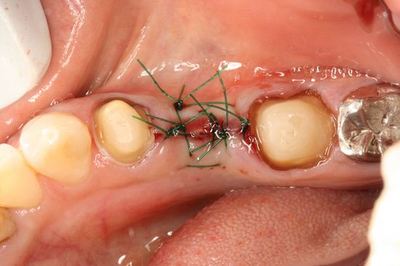

4-0ナイロン縫合糸で縫合しました。